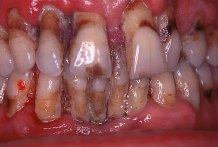

La

periodontitis, que normalmente se denomina "piorrea" (en griego "flujo de

pus"), incluye la inflamaci�n cr�nica y destrucci�n del hueso que soporta los

dientes. Tambi�n, las fibras gingivales y el ligamento periodontal son destruidos y el

borde de las enc�as se desprende de los dientes, formando lo que se llama una bolsa

periodontal en la cual puede aparecer pus. La bolsa periodontal se agranda si el hueso es

destruido m�s severamente y, en consecuencia, los dientes "se aflojan". Al

avanzar la enfermedad los dientes se pueden mover a�n m�s y es frecuente que se forme un

absceso e incluso que se caigan.